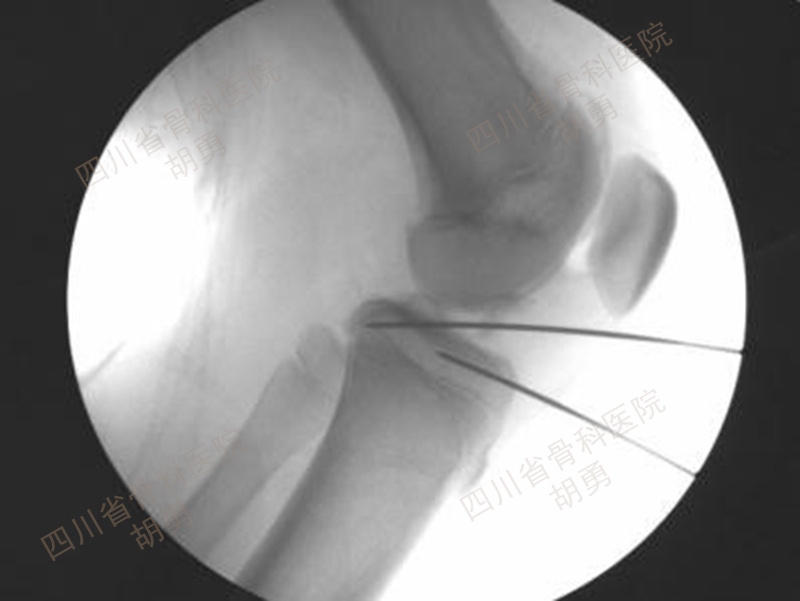

前外侧入口为观察口,于掀起的骨块下,经前下内入口插入直径1.5mm克氏针套管于骨床后壁内、外侧髁间嵴连线中点,方向为前上内斜向后下外,套管和生长板的夹角与术前MRI规划之内排锚钉走向一致,套管指向腓骨小头尖部。经套管钻入直径1.5mm克氏针11mm(与内排锚钉长度一致)。沿内侧胫骨平台髌韧带内缘做3~4cm皮肤纵形切口,止于腓骨小头尖端平面,显露至骨膜。镜下使用一枚静脉留置针经皮肤切口穿过膝横韧带下方,与胫骨平台走行一致。使用直径1.5mm克氏针套管于切口内髌韧带内侧缘旁开10mm,选取静脉留置针与腓骨小头尖端中点,平行静脉留置针方向钻入直径1.5mm克氏针18mm(与外排锚钉长度一致)。拔出定位的静脉留置针,术中透视如图10所示,确认克氏针走行方向、深度和对应锚钉的直径尺寸均在生长板之上,与术前MRI图8规划一致。留置上述两枚克氏针备用。

图10 术中透视内、外排锚钉导针与生长板之空间关系